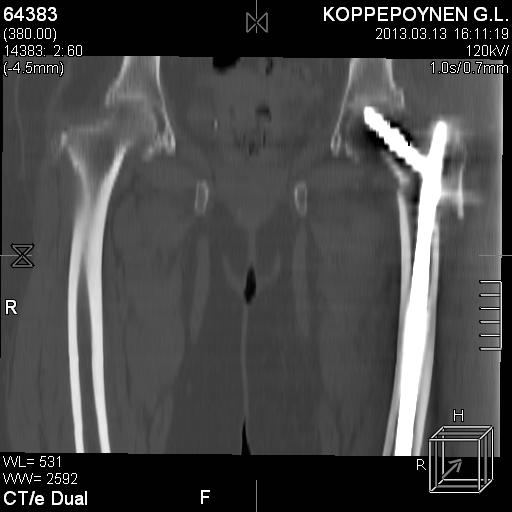

Пациентка, К., 74 лет. В марте 2013 г. упала, диагностирован многооскольчатый чрезподвертельный перелом левой бедренной кости со смещением отломков. 05.03.2013 выполнена закрытая репозиция, остеосинтез левой бедренной кости длинным бедренным гвоздем (ITST, Zimmer) со статическим блокированием отломков. Пациентка в течение 8 недель ходила при помощи ходунков с минимальной нагрузкой на оперированную нижнюю конечность. После выполнения рентгенографии отмечена тенденция к прорезыванию винта и смещение шейки бедренной кости латерально по оси винта (до стержня), нагрузка была ограничена еще на 8 недель. Через 8 недель постепенное градуированное повышение нагрузки до полной. В течение 1,5 месяцев ходила с полной нагрузкой на левую нижнюю конечность, водила автомобиль. Через 1,5 месяца стала отмечать боль в области левого коленного сустава (ранее выполнялось эндопротезирование). Данных за нестабильность компонентов не выявлено. Курсы НПВС по-началу купировали боль в области бедра, через 1 месяц стали малоэффективны. Пациентка наблюдается у невролога в связи с протрузией дисков на уровне пояснично-крестцового отдела позвоночника и периодическими обострениями остеохондороза. С диагностической целью была выполнена блокада бедренного нерва с левой стороны. Боль была полностью купирована, однако возобновилась после прекращения действия анестетика. 10.10.2013 г. пациентка выполнила рентгенографию левого тазобедренного сустава. Выявлен перелом металлофиксатора. Пациентка госпитализирована для лечения.Пациентка до травмы вела активный образ жизни, водила автомобиль. В настоящее время хочет избавиться от болевого синдрома, восстановить опороспособность левой нижней конечности, вернуться к своему обычному ритму жизни.Коллеги три основных вопроса:Какую тактику в данном случае предприняли бы Вы? Варианты удаления металлофиксатора? Чем выполнить реостеосинтез?С уважением, Ершов Дмитрий Сергеевич

Делали КТ после операции.

Непонятно, на какой вопрос с помощью КТ хотели получить ответ? IMHO это было ненужное исследование, все проблемы были видны на обычном снимке. А что на второй проекции? Где аксиальная или профиль?